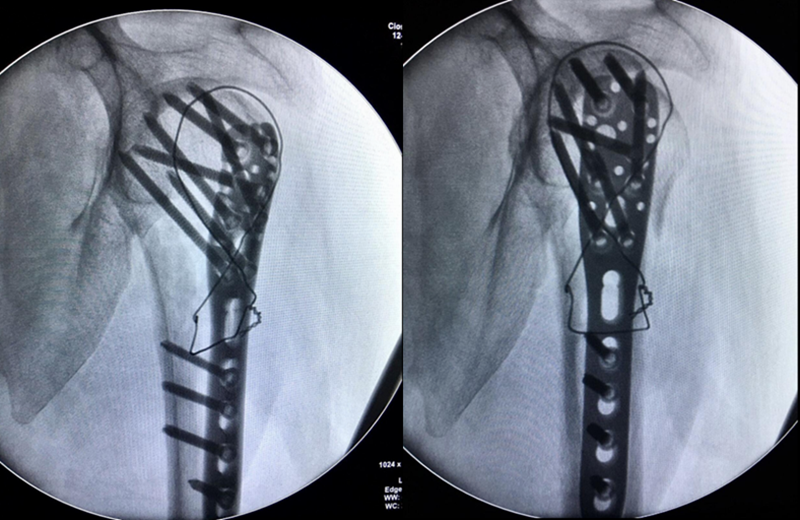

肩前外侧劈三角肌入路,三角肌前束和中间束肌肉间隙进入,双套固定技术加强固定。

图17 术中

术中C-臂检测:

图18 肱骨距螺钉固定确切

术中大幅度肩关节屈伸与外展内收活动,提示骨折坚强固定。